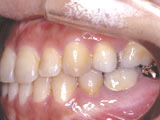

症例2:乱杭歯「歯並びが乱れている」

治療前 治療後